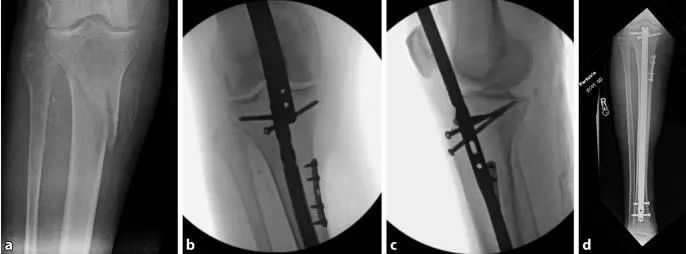

Téhnik séjén anu pohara efektif nyaéta fiksasi samentara tina narekahan dina posisi anatomis (Gbr. 16). Biasana piring tubular sempalan leutik kalawan dua atawa tilu screws konci cortical tunggal bakal nahan narekahan ngurangan salila persiapan terusan akar jeung sisipan paku. piring bakal ngadalikeun duanana displacements. piring kudu ditinggalkeun di tempat salami euweuh celah tetep pikeun nyegah leungitna réduksi nu biasana lumangsung sanggeus panyabutan plat. piring ieu kalawan screw cortical tunggal teu kaku jeung moal mangaruhan stabilitas relatif kuku. Téhnik reset plate tiasa dianggo pikeun narekahan anu kabuka sareng ditutup.

angka 16 A plat ngonci leutik ku screw cortical tunggal tiasa didapet tur dijaga dina reposition anatomis. Dina kalolobaan kasus, piring kudu ditinggalkeun di tempat sanggeus nailing. a deformity valgus awal tina narekahan tibial proksimal. b A pelat narekahan leutik ku screw cortical tunggal disimpen medially pikeun ménta sarta ngajaga repositioning narekahan salila nailing. c piring teu dipiceun sanggeus nailing sabab nyadiakeun stabilitas tambahan